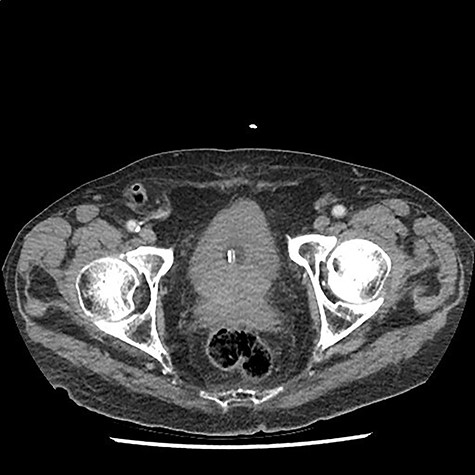

A 90 year old gentleman was admitted on the acute surgical take with right hypochondrium pain. On examination he was pyrexial, tachycardic markedly tender in the right upper quadrant of his abdomen. There was also a reducible non-tender right-sided inguinal hernia present. His past medical history included atrial fibrillation (anti-coagulated with apixaban) alongside ischaemic heart disease, osteoarthritis and a degree of congestive cardiac failure with poor exercise tolerance. On further questioning he had noticed the lump for several weeks but described no tenderness around the lump. Blood workup revealed c-reactive protein of 140 mg/L and white cell count of 15 × 109. He had mildly deranged renal function at baseline consistent with an element of chronic kidney disease. Other blood tests were unremarkable. A diagnosis of acute cholecystitis was made with an incidental finding of right-sided inguinal hernia. He was commenced on intravenous antibiotics and CT scan of the abdomen arranged to ensure no co-existent pathology given his age. CT scan revealed the presence of a right-sided inguinal hernia containing a thickened vermiform appendix with peripheral fat stranding suggestive of acute appendicitis within an Amyand’s hernia (Figs 1 and 2). Additionally, the scan did confirm the concurrent presence of acute uncomplicated cholecystitis. Senior surgical and anaesthetic discussions took place with regards to operating on this patient to treat his appendicitis and repair his hernia. It was universally agreed that the acute cholecystitis could be viably treated with intravenous antibiotics in the interim. However, acute appendicitis, with its risk of complications, warranted further discussion. Following discussion with the patient, consultant physicians, anaesthetists and surgeons, the decision was made to treat both conditions conservatively with antibiotics. The rationale for this was that the patient’s main complaint was that of right upper quadrant pain. He did not have any peritonism or tenderness to his right inguinal canal that would suggest impending perforation or peritonitis. His co-morbidities and age undoubtedly made him a high-risk case for appendicectomy and hernia repair. Most importantly, the patient himself was very reluctant to undergo operation and had full capacity to make this decision, having been made well aware of the risks of not intervening. Ultimately, following a 12 day stay with intravenous antibiotics, physiotherapy input and input from the physicians, he was discharged and to date has suffered no complications of his hernia or gallstone disease.

Axial CT scan demonstrating right-sided inguinal hernia with vermiform appendix located within it, suggestive of Amyand’s hernia.